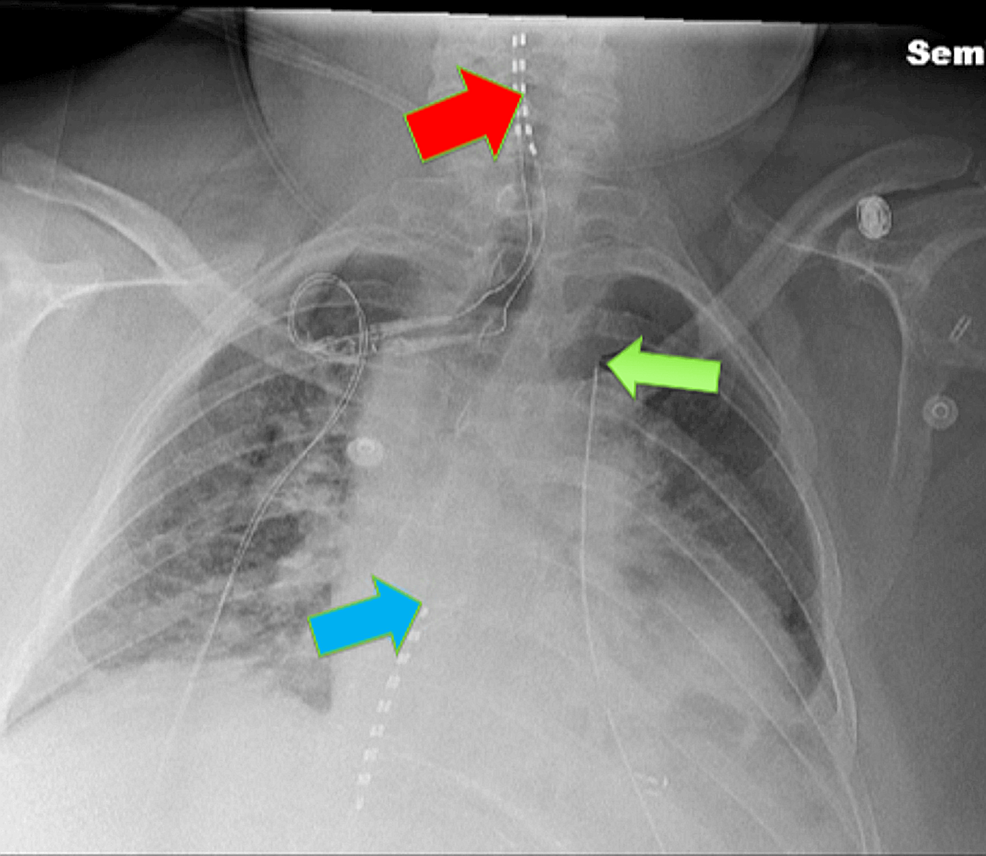

From journals.lww.com

Unilateral Bilevel Erector Spinae Plane Catheters for Flail... A&A Erector Spinae Catheter Vs Epidural Emerging research has shown that the novel erector spinae plane (esp) block, can be employed as a simple and safe alternative analgesic. New pain management techniques to reduce opioid reliance include the erector spinae plane (esp) block. Recently, the erector spinae plane block has been introduced as a practical alternative to the thoracic epidural. The objective of the present study. Erector Spinae Catheter Vs Epidural.